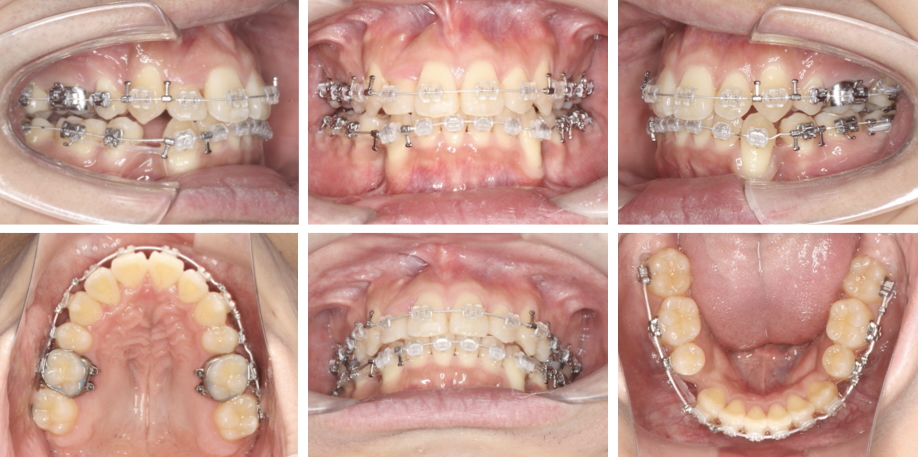

治療開始1年1か月

• 1.初診時年齢:25歳

• 2.主訴:上の歯の真ん中が右にずれていること、右上の前歯が内側にあること、八重歯

• 3.症例のカテゴリー:叢生

• 4.治療のカテゴリー:本格治療

• 5.抜歯:6本(上下顎小臼歯4本、上顎の親知らず2本)

• 6.使用装置:唇側(表側)矯正、トランスパラタルアーチ

• 7.治療期間:1年11か月

• 8.治療にかかった費用:1,028,500円(税込) ※旧料金

初診時、重度の叢生(歯のでこぼこ)を認めました。また叢生に伴い、顔の正中(真ん中)に対して上顎歯列正中は右方に、下顎歯列正中は左方に大きくずれている状態でした。

叢生を解消すること、上下顎歯列正中を顔の正中と一致させることを目的として抜歯を併用し治療を行いました。

患者さんの治療への協力度が大変良好でしたので、治療後はきれいな歯並びを獲得し、また今回掲載していませんが顔の正中に上下顎歯列正中がしっかり一致させることもできました。